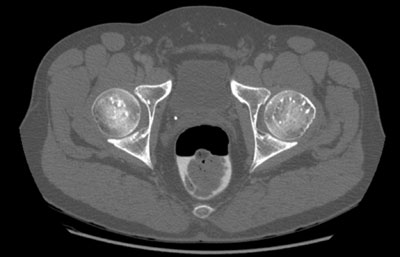

Im Rahmen einer Prostataabklärung wird bei einem 51-jährigen Mann eine Computertomographie des kleinen Beckens durchgeführt.

Knochenbeschwerden werden verneint. Hier ein CT-Schnitt im Bereich der Femurköpfe:

CT kleines Becken (Schnitthöhe Femurkopf)

Wie würden Sie diesen Befund beschreiben?